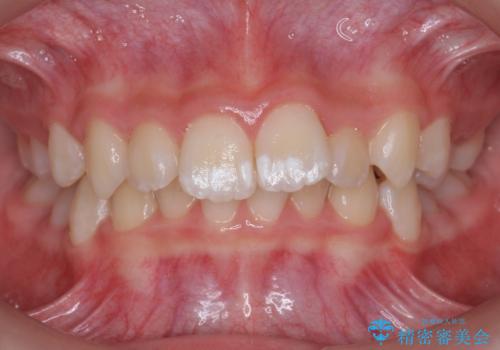

子供の出っ歯 生え代わりと成長期を利用して非抜歯で矯正

- 出っ歯を主訴に来院。

生え代わりを待ってから矯正を始めました。

特に右側のかみ合わせがずれていたため、上の奥歯を後ろに下げています。

下顎も前方に成長し、前歯のかみ合わせも同時に深かったのを浅くすることができました。

矯正は成人でも可能ですが、成人矯正よりも、有利なことがたくさんあります。

10代で矯正を行うと歯の動きも動きやすく、骨の付いてくる度合いもとてもよく、歯肉退縮など副作用が少ないのでお勧めです。移動も早いため、矯正治療期間も短めです。